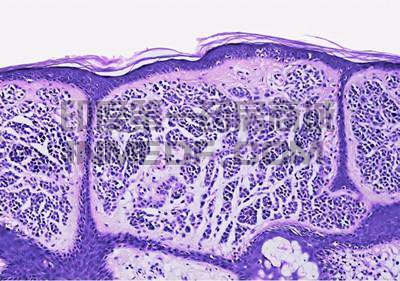

【资讯导读】 基底细胞癌(Basal cell carcinoma,BCC)是一种起源于表皮基底层及其附属器的常见皮肤癌,大多数基底细胞癌在基因中具有突变,这些基因是称为刺猬(Hedgehog)蛋白的细胞信号传导途

基底细胞癌(Basal cell carcinoma,BCC)是一种起源于表皮基底层及其附属器的常见皮肤癌,大多数基底细胞癌在基因中具有突变,这些基因是称为刺猬(Hedgehog)蛋白的细胞信号传导途径的一部分。